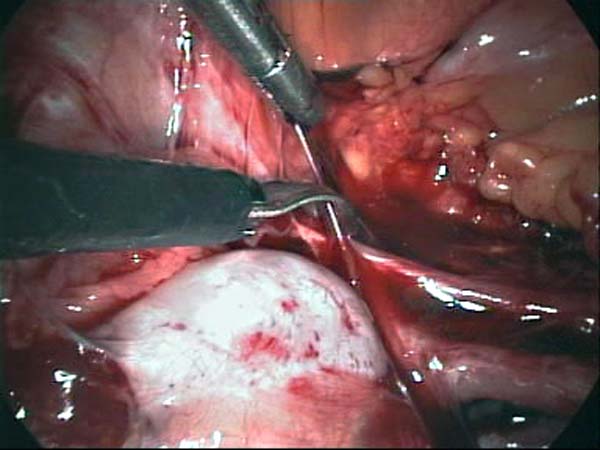

- Laparoscopy Photos 1

- Laparoscopy Photos 2

- Laparoscopy Photos 3

- Laparoscopy Photos 4

Laparoscopy Photos Polycystic Ovaries adhesiolysis IUCD Through Uterine Wall | Dr N Layyous